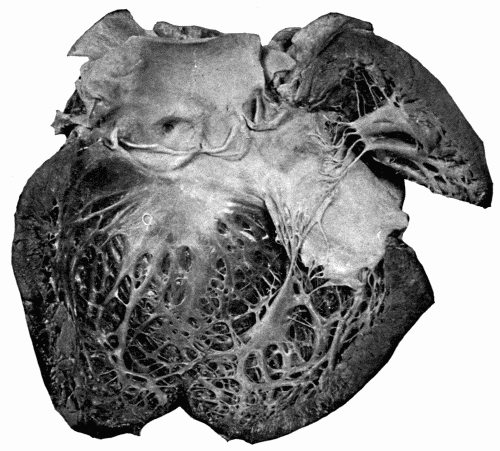

There are many cases of arteriosclerosis which lead to definite interference with the closure of the valves of the heart, particularly the aortic and the mitral. It has been said that puckerings of the valves frequently occur (Fig. 12). This arteriosclerotic endocarditis at times leads to very definite heart lesions, chiefly aortic or mitral insufficiency, or both with, at times, murmurs of a stenotic character at the base. There is rarely true aortic stenosis, however. The murmur is caused by the passage of the blood over the roughened valves and into the dilated aorta. Aortic stenosis is one of the rarest of the valvular lesions affecting the valves of the left heart, and should be diagnosed[61] only when all factors, including the typical pulse tracings, are taken into consideration.

Fig. 12.—Aortic incompetence with hypertrophy and dilatation of left ventricle, the

result of arteriosclerosis affecting the aortic valves. Note how the valves have been curled,

thickened, and shortened, the edges of valves being a half inch below the upper points

of attachment. The anterior coronary artery is shown, the lumen narrowed. (Reduced

one-half.) Fig. 12.—Aortic incompetence with hypertrophy and dilatation of left ventricle, the result of arteriosclerosis affecting the aortic valves. Note how the valves have been curled, thickened, and shortened, the edges of valves being a half inch below the upper points of attachment. The anterior coronary artery is shown, the lumen narrowed. (Reduced one-half.)